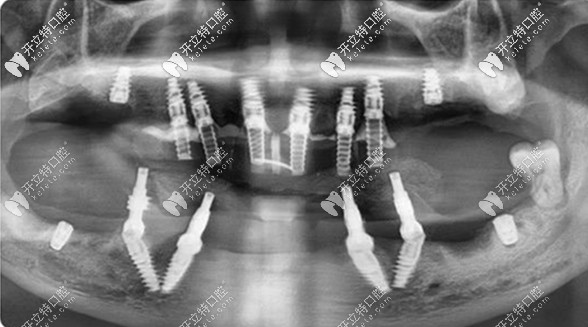

【終期方案為——all-on-4/6全口即拔即種 即刻負(fù)重的種植方案】

在充分了解了鄧?yán)蠋煹目谇磺闆r和訴求后,擅長(zhǎng)全口缺牙修復(fù)的王鋒醫(yī)生為她定制了全口即拔即種的方案。

全口拔牙+即刻種牙+當(dāng)天用牙,對(duì)家在瀘州的鄧?yán)蠋焷?lái)說(shuō),不僅避免了來(lái)回奔波,還避免了缺牙期對(duì)自己形象、工作和日常生活的影響。